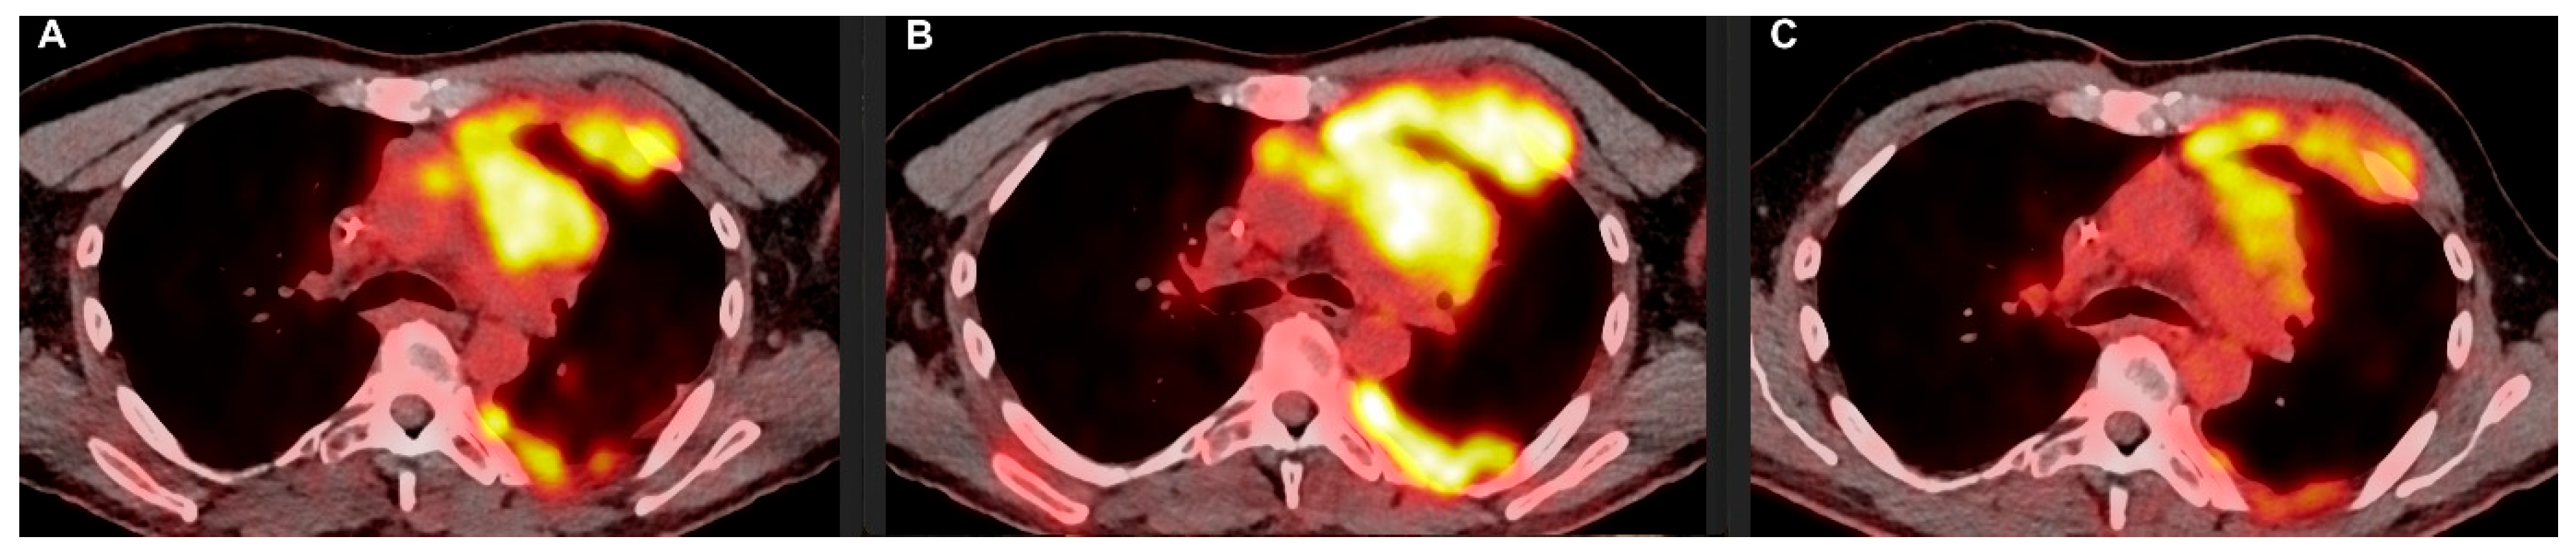

2. Case Report